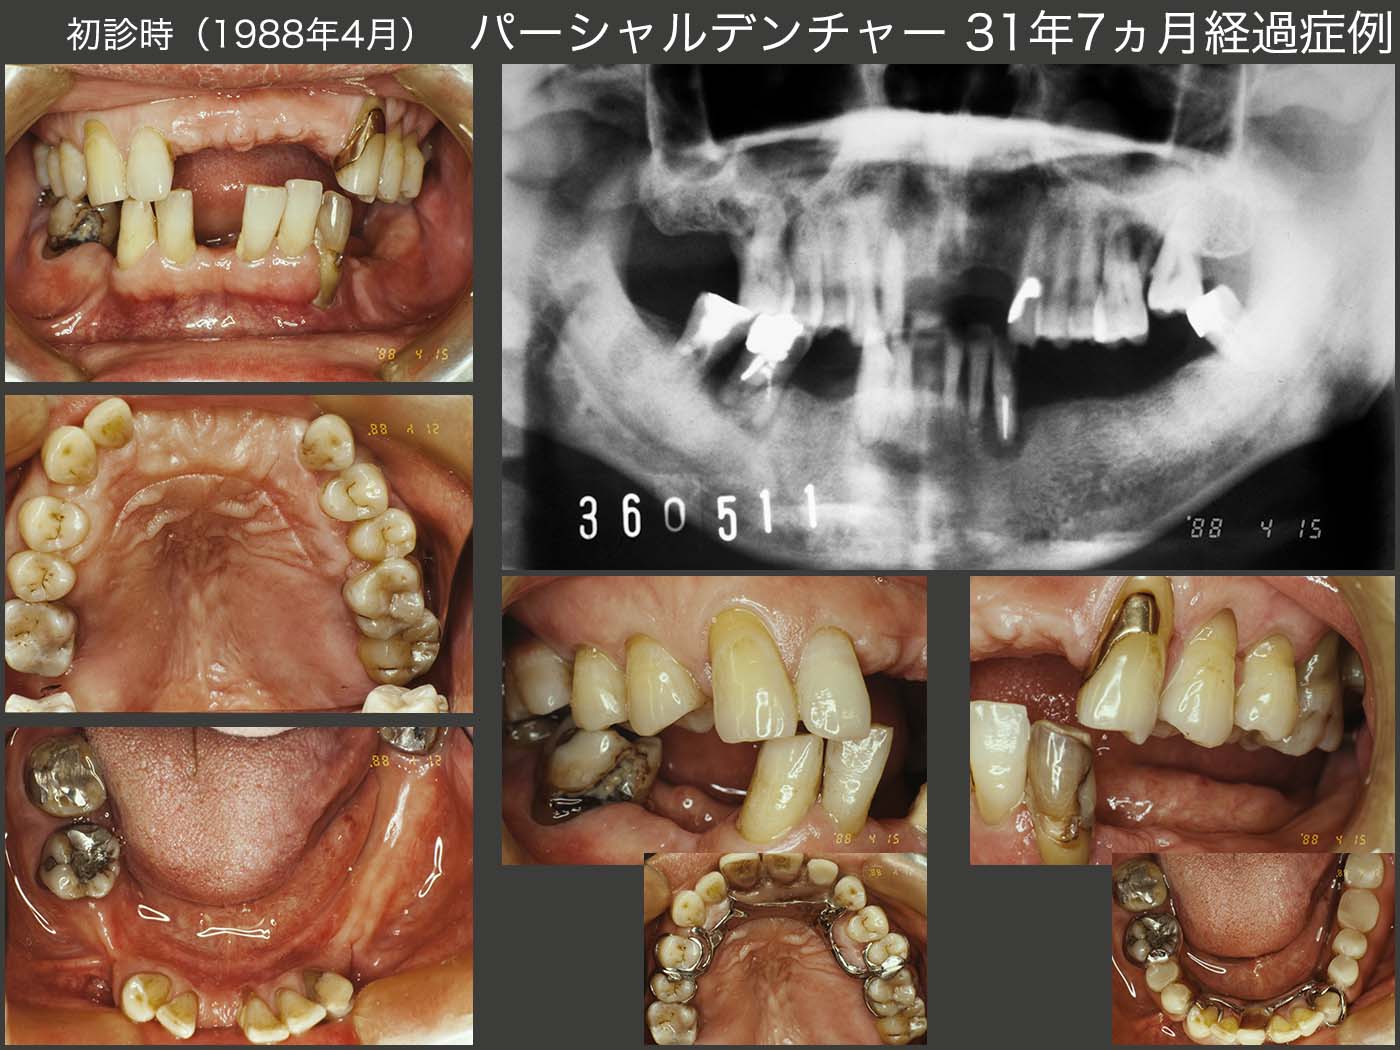

【始めにこちらをお読みください】・本商品は裁断済みです。・スキャン目的のため、1ページずつバラバラの状態になっています。・裁断済みのためやや傷や汚れありのコンディションにしていますが、中のページにつきましては、書き込みや大きな汚れはなく、比較的良好な状態です。・裁断済みであることをご理解のうえ、ご購入をお願いいたします。・裁断済みを理由とした返品はご容赦ください。・まとめ買いご希望の方はお気軽にご申請下さい。長期症例に基づいたパーシャルデンチャーの包括的医療における重要性を解説した一冊。- 出版社: クインテッセンス出版定価(本体12,000円+税)ご覧いただきありがとうございます。